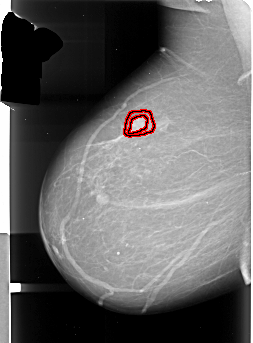

A_1004_1.RIGHT_MLO

FILE: A_1004_1.RIGHT_MLO.OVERLAY

TOTAL_ABNORMALITIES 1

ABNORMALITY 1

LESION_TYPE MASS SHAPE IRREGULAR MARGINS ILL_DEFINED

ASSESSMENT 5

SUBTLETY 5

PATHOLOGY MALIGNANT

TOTAL_OUTLINES 1

BOUNDARY